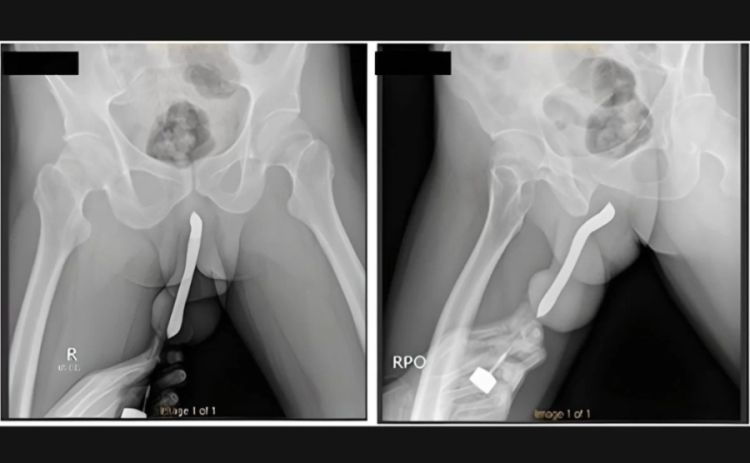

Um homem de 43 anos, da Indonésia, precisou passar por uma cirurgia após uma escova de dentes quebrar dentro do pênis dele durante uma relação sexual. O objeto foi inserido no órgão sexual pelo próprio paciente.

Os médicos do Hospital Geral Acadêmico Soetomo, na cidade de Surabaya, contam que o homem esperou 12 horas para procurar atendimento médico. Ao chegar ao pronto-socorro, o pênis dele estava muito inchado e disforme.

Ele admitiu para os socorristas que enfiou a escova de dentes no órgão sexual para “satisfação pessoal”. Também acrescentou que já havia feito um pequeno corte no órgão para conseguir inserir objetos no local com mais facilidade.

O indonésio passou por uma cirurgia de duas horas e recebeu alta três dias depois. Na consulta de retorno, um mês depois, ele disse não ter sofrido complicações e conseguir urinar normalmente. O pênis também voltou ao formato original.